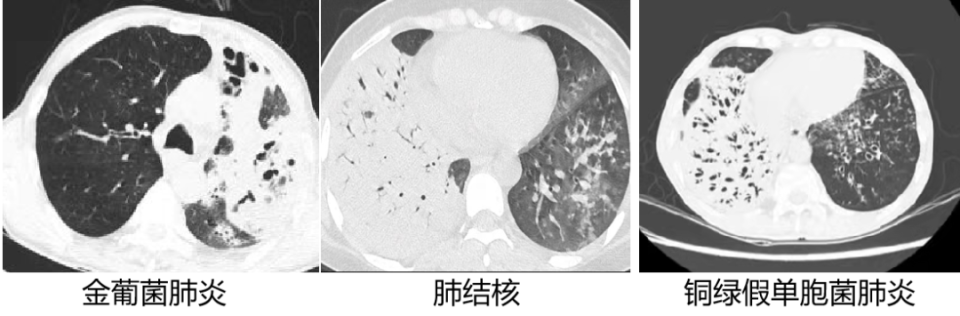

五. 3 种肺炎常见的致病菌

1. 肺泡性肺炎(大叶性肺炎):肺炎链球菌肺炎、肺炎克雷伯杆菌肺炎、军团菌肺炎及肺隐球菌病。

2. 支气管肺炎(小叶性肺炎):金黄色葡萄球菌肺炎、铜绿假单胞菌肺炎、流感嗜血杆菌肺炎、大肠埃希菌肺炎、阴沟杆菌肺炎、肺结核及非结核分枝杆菌肺炎、支原体肺炎、肺念珠菌病、丝状真菌肺病等。